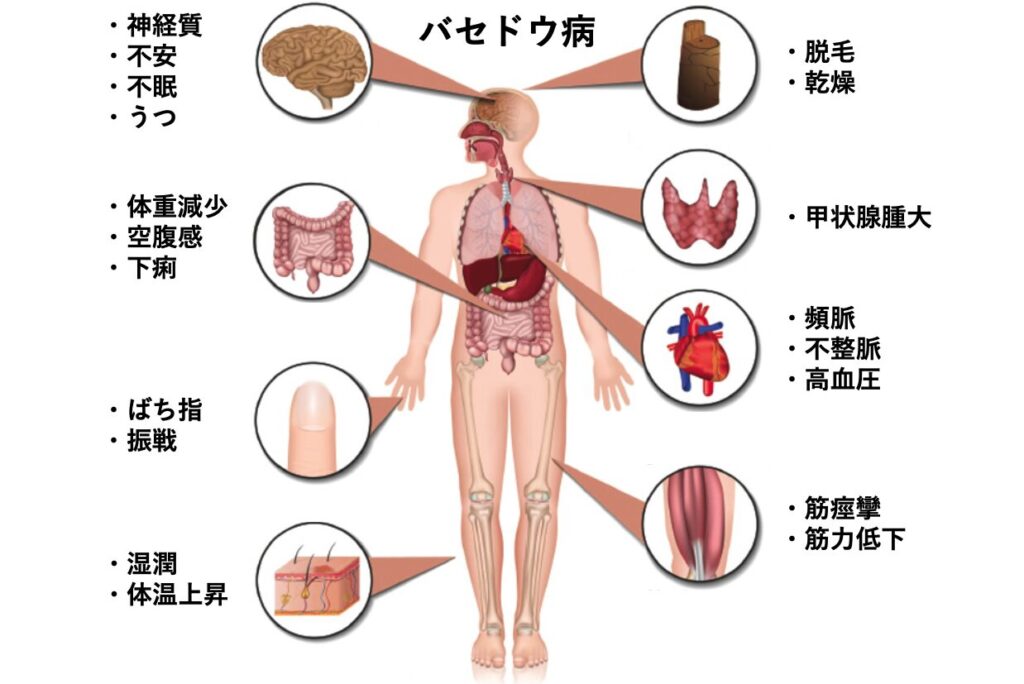

バセドウ病(Graves’ disease)

バセドウ病は自己免疫疾患であり、体が自分の組織に対する抗体を産生する病気です。この抗体により、甲状腺は甲状腺ホルモンを作りすぎてしまいます。動悸、体重減少、手の震えなどの症状が出現します。診断のために血液検査や放射性物質を用いた画像検査を行い、治療としては抗甲状腺薬の内服、放射性ヨード、または甲状腺を切除する手術を行います1)。

症状